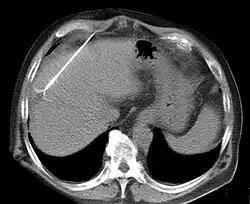

RFA may be performed to treat tumors in the lung,[10][11][12] liver,[13] kidney, and bone, as well as other body organs less commonly. Once the diagnosis of tumor is confirmed, a needle-like RFA probe is placed inside the tumor. The radiofrequency waves passing through the probe increase the temperature within tumor tissue, which results in destruction of the tumor. RFA can be used with small tumors, whether these arose within the organ (primary tumors) or spread to the organ (metastases). The suitability of RFA for a particular tumor depends on multiple factors.